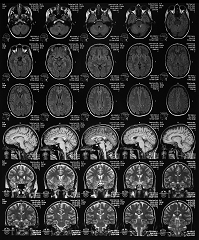

МРТ как ключевой инструмент в диагностике и мониторинге РС

Магнитно-резонансная томография (МРТ) – это неинвазивный метод визуализации‚ который позволяет получить детальные изображения головного и спинного мозга. МРТ является ключевым инструментом в диагностике и мониторинге РС‚ поскольку позволяет выявлять очаги демиелинизации – участки повреждения миелина‚ характерные для этого заболевания.

Однако анализ МРТ-изображений требует времени и опыта. Врачи-радиологи должны внимательно изучить каждый снимок‚ чтобы выявить и оценить очаги демиелинизации. Этот процесс может быть трудоемким и подвержен ошибкам‚ особенно при большом количестве снимков или сложных случаях.